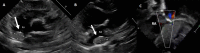

The Society for Cardiovascular Magnetic Resonance (SCMR) is an international society focused on the research, education, and clinical application of cardiovascular magnetic resonance (CMR). Case of the week is a case series hosted on the SCMR website ( https://www.scmr.org ) that demonstrates the utility and importance of CMR in the clinical diagnosis and management of cardiovascular disease. Each case consists of the clinical presentation and a discussion of the condition and the role of CMR in diagnosis and guiding clinical management. The cases are all instructive and helpful in the approach to patient management. We present a digital archive of the 2020 Case of the Week series of 11 cases as a means of further enhancing the education of those interested in CMR and as a means of more readily identifying these cases using a PubMed or similar search engine.